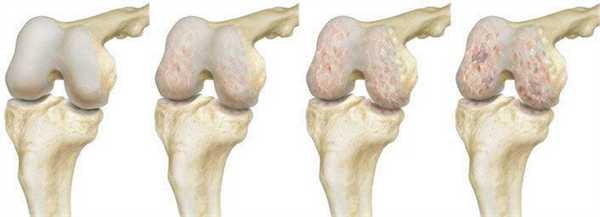

Операция по замене коленного сустава является одним из вариантов лечения коленного сустава, поврежденного остеоартритом. Остеоартроз развивается вследствие разрушения суставного хряща и подлежащей кости.

Динамика разрушения хрящевой поверхности.